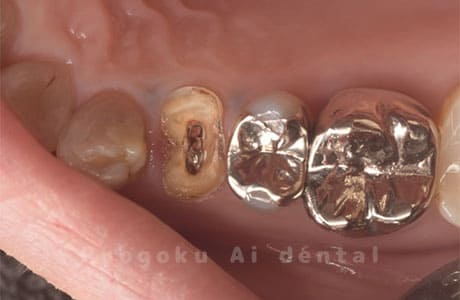

Case02

- 縁下カリエス、慢性根尖性歯周炎、不良補綴

- 治療期間

- 約6ヶ月

- 治療内容

- クラウンレングスニング、マイクロエンド、フルジルコニアクラウン

- 治療費用

- 約840,000円

虫歯が神経まで及ぶと共に、歯茎の中まで虫歯が及んでいました。根の治療(マイクロエンド・根管治療)を行なった後、クラウンレングスニング・歯周外科を行い、ジルコニアの被せ物を行った患者様です。

<リスク・副作用>

過度の咬合や衝撃で割れることがあります。